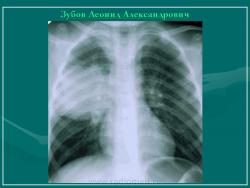

Эхинококкоз ( Ecninococcus unilocularis )

Сердце